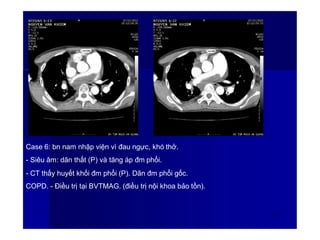

Case 6: bn nam nhập viện vì đau ngực, khó thở.

- Siêu âm: dãn thất (P) và tăng áp đm phổi.

- CT thấy huyết khối đm phổi (P). Dãn đm phổi gốc.

COPD. - Điều trị tại BVTMAG. (điều trị nội khoa bảo tồn).